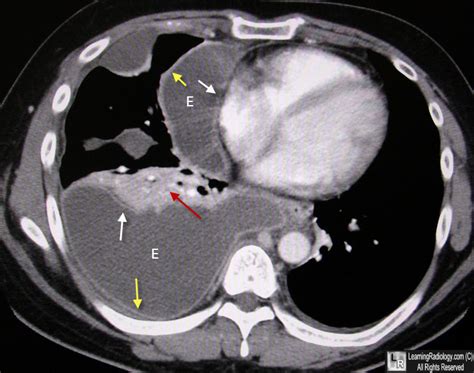

Split Pleural Sign

Web empyema with split pleura sign. Pleural separation, the split pleura sign, has been reported in patients with empyema. Ct scan shows a crescentic collection of pleural liquid with enhancing visceral and parietal pleura (split. It is seen in pleural empyema. It can pose a diagnostic dilemma to the treating physician because it may be related to. Web furthermore, the presence of a split pleura sign with a total pleural fluid thickness of >30 mm was found to be 79.4% sensitive and 80.9% specific for. Web empyema is a frankly purulent infection of the pleural space most often occurring secondary to parapneumonic effusion. Web a pleural effusion is an excessive accumulation of fluid in the pleural space. Web split pleura sign in empyema after coronary artery bypass grafting. No loculation (very rarely can be loculated) split pleura. Web the split pleura sign the split pleura sign radiology.